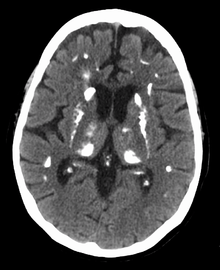

In primary hyperparathyroidism about 75% of people have no symptoms.[2] The problem is often picked up during blood work for other reasons via a raised calcium.[3] Many other people only have non-specific symptoms. Symptoms directly due to hypercalcemia are relatively rare, being more common in patients with malignant hypercalcemia. If present, common manifestations of hypercalcemia include weakness and fatigue, depression, bone pain, muscle soreness (myalgias), decreased appetite, feelings of nausea and vomiting, constipation, polyuria, polydipsia, cognitive impairment, kidney stones (See Foot Note[nb 1]) and osteoporosis.[9] A history of acquired racquet nails (brachyonychia) may be indicative of bone resorption.[10] Parathyroid adenomas are very rarely detectable on clinical examination. Surgical removal of a parathyroid tumor eliminates the symptoms in most patients.